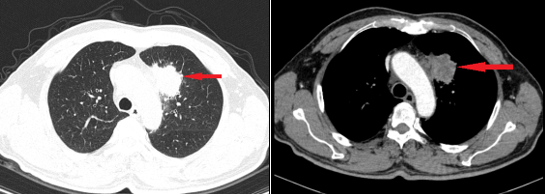

- Chụp cắt lớp vi tính lồng ngực: Hình ảnh khối nhu mô thùy trên phổi trái kích thước 38x38x59 mm, bờ tua gai co kéo gây giãn các nhánh phế quản lân cân, ngấm thuốc mạnh không đều sau tiêm, xâm lấn trung thất. Hạch trung thất dưới carina, dọc quai động mạch chủ và rốn phổi trái, hạch lớn nhất kích thước 14x11 mm.

Hình 2: Hình ảnh cắt lớp vi tính lồng ngực lúc mới: khối thùy trên phổi trái xâm lấn trung thất (mũi tên đỏ).

Hình 3: Hình ảnh cắt lớp vi tính lồng ngực lúc mới chẩn đoán: hình ảnh hạch trung thất cạnh quai động mạch chủ (hình bên trái), hạch rốn phổi trái (hình bên phải).